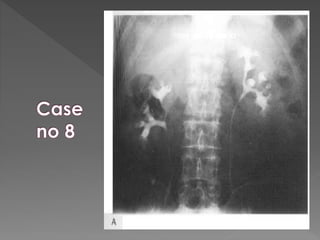

 Acute Obstruction: There is delay in opacification of the collecting system.  Delay may be considerable up to 24 hrs or more.  It is then necessary to perform additional films

 Time intervalb/w films is doubled 0.5 hrs/ 1 hr/ 2 hrs/ 4 hrs/ 16 hrs/ 24 hrs as necessary.  To minimize the radiation exposure If there is no opacification at 30 mins it is usually unhelpful to perform next film before 4 hrs